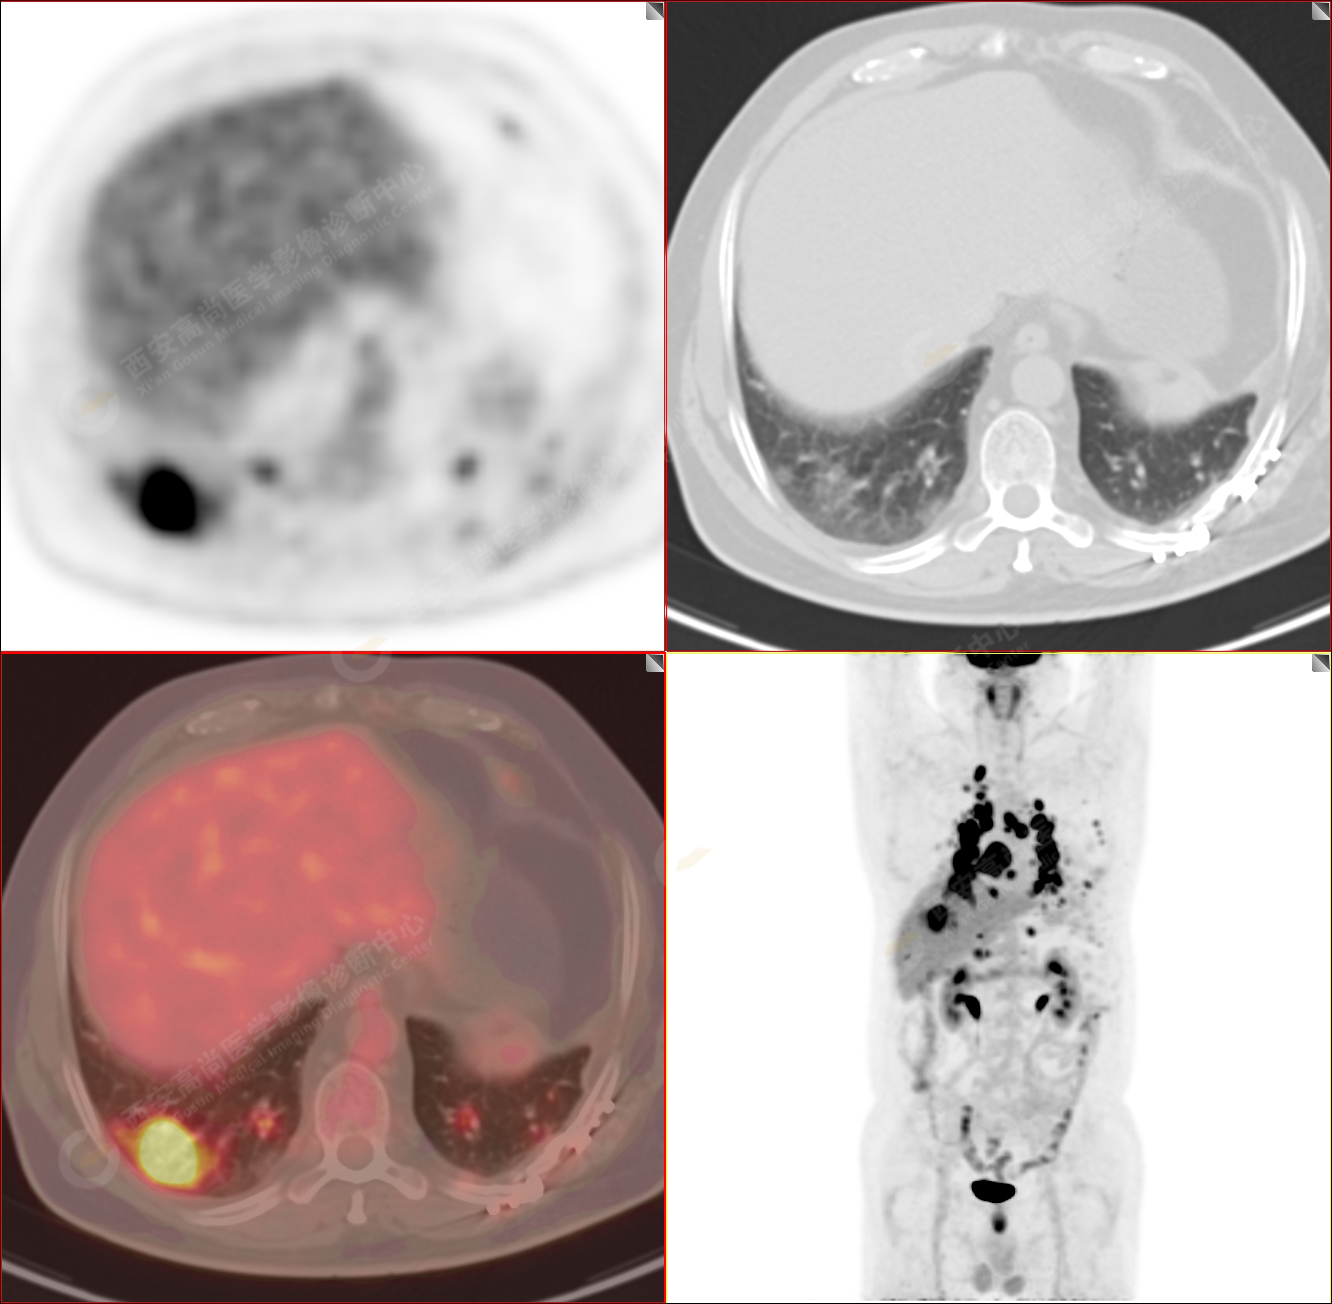

男性,53歲,頭暈半月入院,CT發(fā)現(xiàn)肺內(nèi)腫塊,雙肺多發(fā)大小不等實(shí)性及粟粒樣結(jié)節(jié),雙肺門(mén)及縱隔多發(fā)腫大淋巴結(jié)。病程中無(wú)發(fā)熱、胸悶氣及胸部不適。既往:左側(cè)肋骨外傷史。

PET/CT圖像